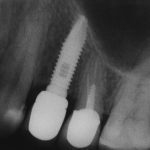

Кстати, обрати внимание на ширину альвеолярного гребня (левая картинка). Она чуть меньше 3 мм. Это объясняет, почему я засомневался в возможности установки имплантатов одновременно с остеопластикой. Понятно и без КЛКТ.

Возвращаемся к основной операционной области. Еще раз посмотрим на альвеолярный гребень, поофигеваем от его ширины и моих грандиозных планов:

Я зафиксировал костный блок практически без адаптации на несколько винтов. Обрати внимание, что винты находятся в зоне, где не планируется установка имплантатов. Фиксация должна быть надежной, поскольку мне еще предстояла подготовка лунок для имплантатов. Трех винтов для этого вполне достаточно.

Глянем на то, что получилось: